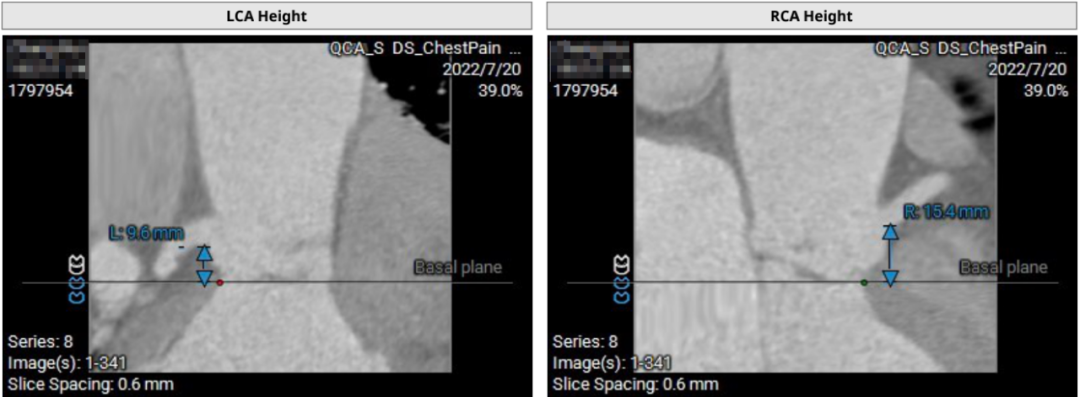

患者71岁女性,诊断为主动脉瓣重度狭窄合并心功能不全,瓣口面积仅0.5cm²,跨瓣压差超过50mmHg,且EF仅27%,心功能极差。术前CT检查瓣环周长72.2mm,LVOT呈喇叭型。CT检查同时发现患者入路血管狭窄,股动脉直径5.3cm,锁骨下和颈内动脉直径都小于5.0cm,对操作造成了一定困难。

患者64岁男性,Type 0 型二叶瓣、横位心。主动脉瓣中度狭窄,重度反流,瓣环周长92.0mm,平均径29.0mm。LVOT周长98.7mm,升主扩张,窦部结构极限,锚定能力极限。入路两侧血管轻度迂曲,分叉高度可,两侧血管内径均>8mm。

患者左、右冠高度,瓣叶长度,窦宽相对瓣膜均尚可,冠脉风险低。但由于患者重度AR,可能因植入深度和选择大型号瓣膜,带来较高的传导阻滞风险。其次,患者升主扩张,存在破裂风险。最后,患者是横位心,瓣环及流出道结构大,术中瓣膜释放的位置达到了极限,瓣膜释放后可能会发生位移,有瓣中瓣风险。

“要仔细观察瓣叶到底有没有增厚,最重要的是确定瓣环、LVOT和升主动脉这三个位置的锚定条件,如果三个位置都有锚定,那基本上比较可靠。如果只有两个锚定区,那要看瓣环情况,如果瓣环加瓣叶有增厚,甚至有一点点轻到中度的狭窄,这样比较好。”

首先,最重要的是观察瓣环结构,理论上如果瓣环周长超过85mm,尽量就不做;第二,看流出道情况,最好是直筒状的,瓣环和瓣下4mm的直径比值,理论上不能超过1:1.1,如果超过1.1以上就变成喇叭状,也不建议做;第三,避免存在升主动脉显著扩张,如果扩张明显,无法提供有效的锚定。总体来说,最主要的一定是瓣环直径,瓣叶有没有增厚,瓣叶有没有钙化,瓣环能否有效固定住植入的瓣膜。瓣环的固定和锚定条件,是反流患者能否进行TAVR的决定因素。